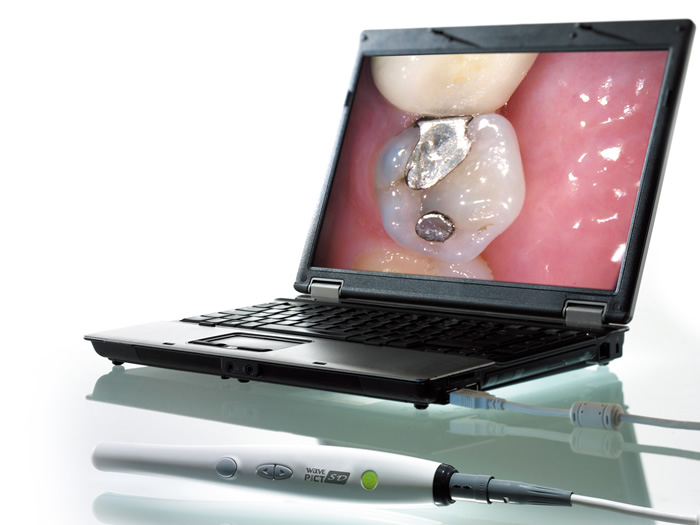

口腔内カメラを使用

術前・術後について、わかりやすい説明を心がけております。従って患者様はご自身の口腔内でどのような治療を行っているか把握できます。

術前・術後について、わかりやすい説明を心がけております。従って患者様はご自身の口腔内でどのような治療を行っているか把握できます。